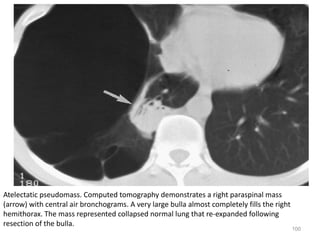

Atelectatic pseudomass. Computed tomography demonstrates a right paraspinal mass

(arrow) with central air bronchograms. A very large bulla almost completely fills the right

hemithorax. The mass represented collapsed normal lung that re-expanded following

resection of the bulla.